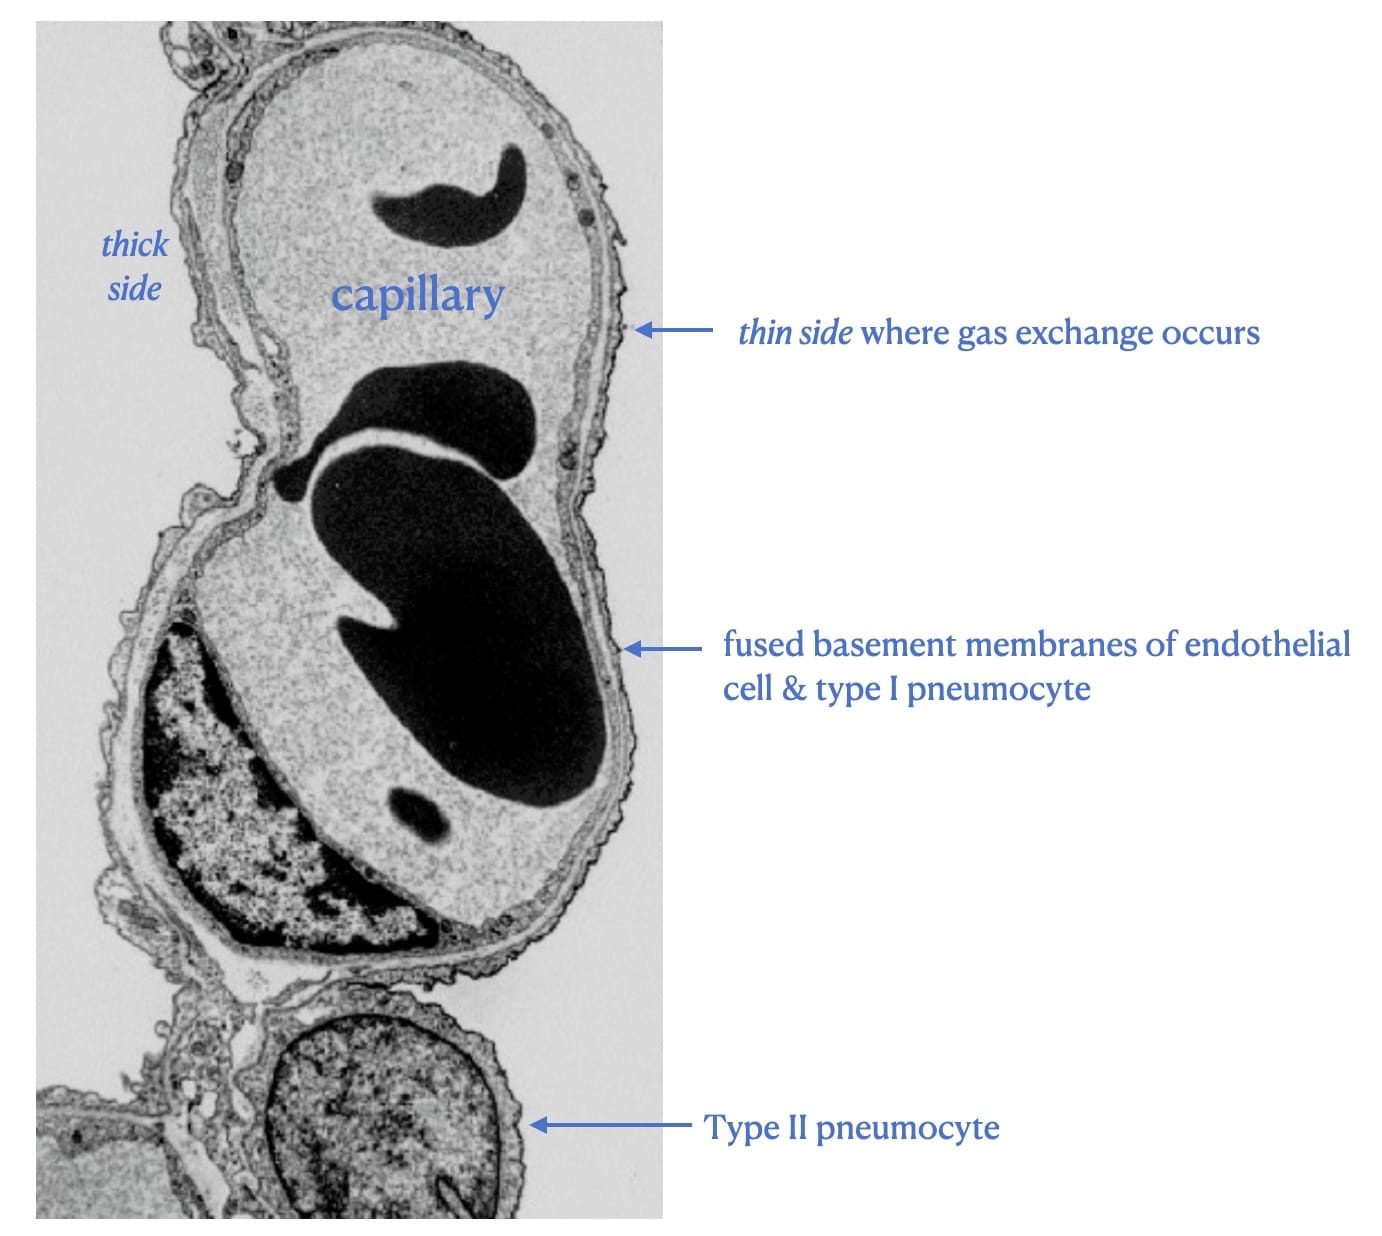

Acute Lung Injury - What is injured ?

The alveolar-capillary barrier (electron microscopy)

The consequence is the passage of large molecules and water directly into alveoli.

The pathologic counterpart is Diffuse Alveolar Damage